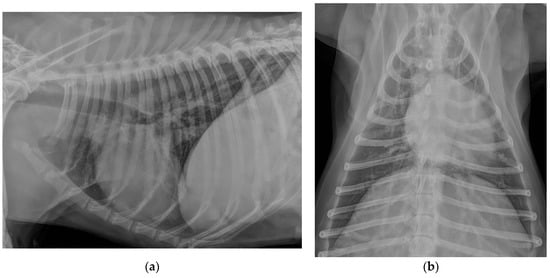

2.1. Case Description and Clinical Investigations